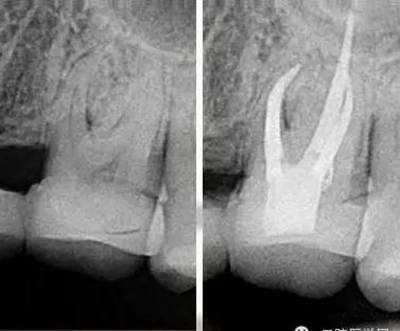

我喜歡比較有挑戰(zhàn)的工作,在牙科治療中最有挑戰(zhàn)的治療之一就是根管治療。牙齒的根管系統(tǒng)非常復(fù)雜,就像一顆大樹,有主干也有枝葉,要把這么復(fù)雜的根管系統(tǒng)治療到位很有挑戰(zhàn)。它需要掌握的技術(shù)比較多,涉及到的器械是最多的,治療一顆牙常常需要擺出3大桌的工具。當(dāng)你花了很長(zhǎng)時(shí)間把一顆牙的根管治療治療到位以后,看著術(shù)后的X線片,感覺就像在欣賞一件藝術(shù)作品,非常美,非常有成就感。

把根管感染清理出來,除了旋轉(zhuǎn)鎳鈦器械的切屑往外帶出來以外還有一些殘留的碎屑粘在根管壁上,要把這部分碎屑沖出來,就會(huì)用到根管超聲器械或者聲波器械,通過高頻震動(dòng),帶動(dòng)根管內(nèi)部沖洗液的震動(dòng),從而讓那些殘留碎屑從根管壁上脫落下來并且被沖出來。好了,現(xiàn)在根管內(nèi)部都清理干凈了,剩下這個(gè)空腔我們要把它完全的填起來,不讓外界的細(xì)菌進(jìn)入內(nèi)部。這個(gè)時(shí)候我們會(huì)用到一種材料叫牙膠,這種材料比較穩(wěn)定,可以長(zhǎng)期的存在根管里?,F(xiàn)在比較先進(jìn)的牙膠充填是熱牙膠充填系統(tǒng),把牙膠加熱到一定溫度后具有流動(dòng)性,通過垂直加壓,讓它自動(dòng)的把整個(gè)根管系統(tǒng)都填滿。